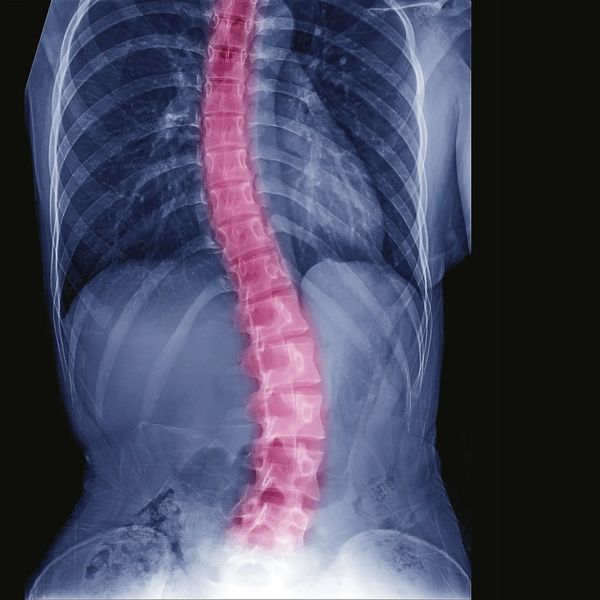

Scoliosis is a condition where the spine curves sideways, often forming an S or C shape. It can affect people at any age, but it's most commonly diagnosed in children and teenagers, particularly during growth spurts between the ages of 10 and 18. This type is known as idiopathic scoliosis, meaning the exact cause isn’t known—but it often develops as kids grow quickly.

Scoliosis can range from mild to more noticeable spinal curves. In many cases, especially for children and teens, it's important to monitor and manage the condition to prevent it from getting worse.

Chiropractic care can be a valuable part of a comprehensive approach to scoliosis. Chiropractors focus on gently improving spinal alignment, strengthening the muscles that support the spine, and encouraging better posture. These techniques can help relieve discomfort, improve mobility, and support a more balanced, healthier spine.